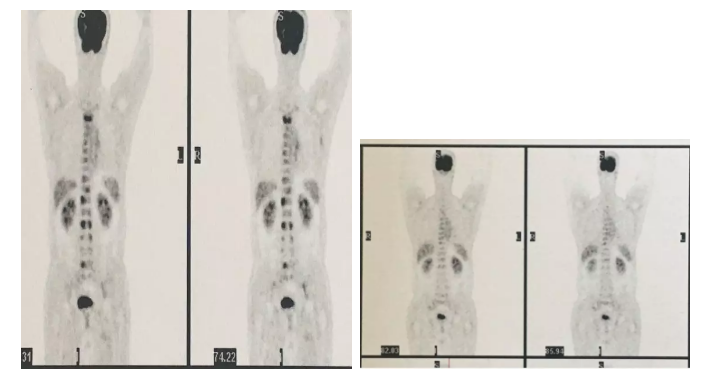

2、肺癌全身骨转移患者

四期肺腺癌,同时伴随脑转移,纵膈转移、全身骨转移,MTCA-CTL免疫疗法联合靶向治疗一疗程后,纵膈淋巴结转移灶明显缩小,全身骨转移基本消失!